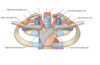

Label the image of coronary sulcus

Label this image of the mediastinum and what type of image is it

- Cross section through the mediastinum